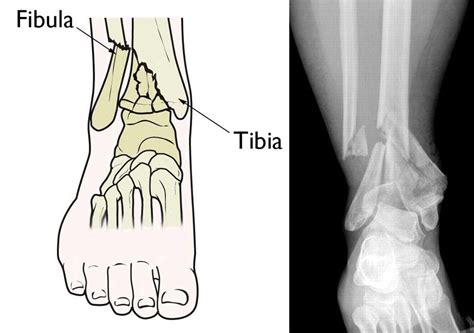

A pilon fracture, is a fracture of the distal part of the tibia, involving its articular surface at the ankle joint. A pilon frcture, also known as a tibial plafond fracture,and include a distal tibial metaphyseal fracture with fracture of medial malleolus, anterior margin of tibia, and transverse fx of posterior tibial. Seems as if i broke some metatarsuls in the left ankle as well, along with a chip avulsion fracture and severe sprain, non operative.

Most of the time, it involves breaks in both the tibia and fibula of the lower leg.

A pilon fracture, is a fracture of the distal part of the tibia, involving its articular surface at the ankle joint. A pilon fracture, is a fracture of the distal part of the tibia, involving its articular surface at the ankle joint. Once again, it's been ages since my last update, so i wanted to check in as i still receive a lot of emails with questions regarding my recovery. The nature of the pilon fracture has caused evolution of treatment methods and its historically high rate of complication and poor outcome continue to direct. The mean time for fracture healing was 3.6 months (range: The fracture involves the larger bone of the lower leg (tibia), and extends into the weight bearing surface of the ankle joint. If you have a pilon fracture reach out today to see what treatment plan is right for you? Commonly, the fibula bone in the ankle is broken as well. After recovery from pilon fractures, many patients continue to have debilitating pain and ankle stiffness. A pilon frcture, also known as a tibial plafond fracture,and include a distal tibial metaphyseal fracture with fracture of medial malleolus, anterior margin of tibia, and transverse fx of posterior tibial. Ryan finnan, md major usaf mc university of cincinnati medical center. Most of the time, it involves breaks in both the tibia and fibula of the lower leg. Seems as if i broke some metatarsuls in the left ankle as well, along with a chip avulsion fracture and severe sprain, non operative. Pilon fractures are caused by rotational or axial forces, mostly as a result of falls from a height or motor vehicle accidents. Pilon fractures in the distal tibia result from axial forces that can range from low to high energy and produce a spectrum of articular and metaphyseal injuries. Pilon fractures are rarely accompanied by ligament injuries, and. Also known as a tibial plafond fracture.